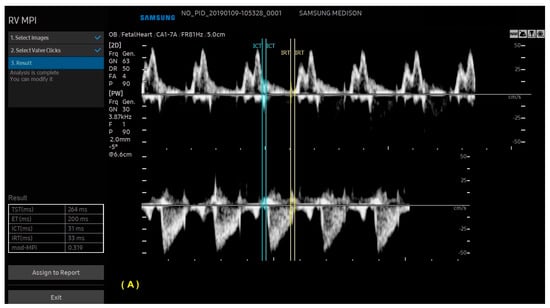

With ML, the ultrasound machine is able to automatically obtain cardiac measurements based on the identification of anatomical cardiac structures, reducing the scan time and inter-observer measurement variation. In this scenario, not only anatomical, but also functional parameters (such as the myocardial performance index) can be automatically measured. With the advances in AI, this technology has been increasingly added to ultrasound devices, such as obstetric ultrasound, and is applicable to three areas: structure identification, automatic measurements, and the classification of diagnosis. AI software (Heart Assist and MPI+—Samsung Healthcare, Gangwon, South Korea) can identify the fetal heart structures and perform automatic biometric and the right and left myocardial performance index measurements, respectively (Figure 12 and Figure 13) [42,43,44].

Figure 13.

Artificial Intelligence (MPI+) The ultrasound machine is able to select Doppler images of the ventricular inflow and outflow tracts, identify valve clicks, and perform cardiac cycle time measurements. (A) Modified myocardial performance index (mod-MPI) was automatically calculated for the right (A) and left (B) ventricles of a fetus in the first trimester of pregnancy. LV: left ventricle; RV: right ventricle; ET: ejection time; ICT: isovolumetric contraction time; IRT: isovolumetric relaxation time.